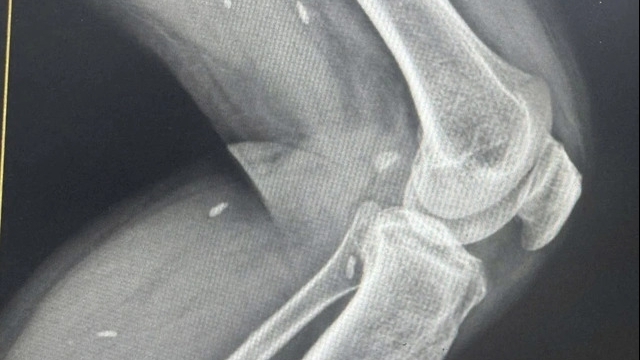

Ngoài những lúc nhậu nhẹt cùng bạn bè, mỗi ngày Nong Om đều tự uống rượu một mình. Người thân của Nong Om cho biết, thời gian đầu anh chỉ uống ít, nhưng khi đã quen rượu, đỉnh điểm có thời gian chàng trai trẻ uống tới 2 chai một ngày. Gần đây nhận thấy Nong Om có dấu hiệu bị vàng da, vàng mắt, bụng sưng to, gia đình đã đưa anh đến bệnh viện.

Sau khi kiểm tra, bác sĩ chẩn đoán Nong Om đang ở giai đoạn cuối của bệnh xơ gan, cơ thể bị hủy hoại bởi chất độc của rượu, thời gian sống còn lại chỉ tính bằng tháng. Để tập trung điều trị, bác sĩ cố gắng cảnh báo anh không được nạp thêm chất cồn vào cơ thể nữa nhưng vì nghiện nặng Nong Om vẫn giấu mọi người bí mật uống rượu.

Khoảng một tuần sau, Nong Om bị chảy máu mũi không ngừng. Anh được chuyển vào phòng cấp cứu trong tình trạng nội tạng chảy máu, cơ thể phù nề, khó thở. Bác sĩ cho biết trước trước khi trút hơi thở cuối cùng, Nong Om đã phải chịu rất nhiều đau đớn và qua đời ở tuổi 26 vì mất máu quá nhiều.

- Gây bệnh gan: Gan là nơi xử lý tất cả chất cồn mà bạn uống vào người. Trong quá trình này, nó phải hứng chịu một đợt tấn công của rất nhiều độc tố. Nếu tần suất uống rượu lớn, theo thời gian gan sẽ tích tụ nhiều chất béo gọi là gan nhiễm mỡ. Chất béo hạn chế lưu lượng máu đến các tế bào gan, khiến chúng bị suy và mất chức năng, trở thành mô sẹo. Các mô này không thể hoạt động được nữa và được gọi là xơ gan.